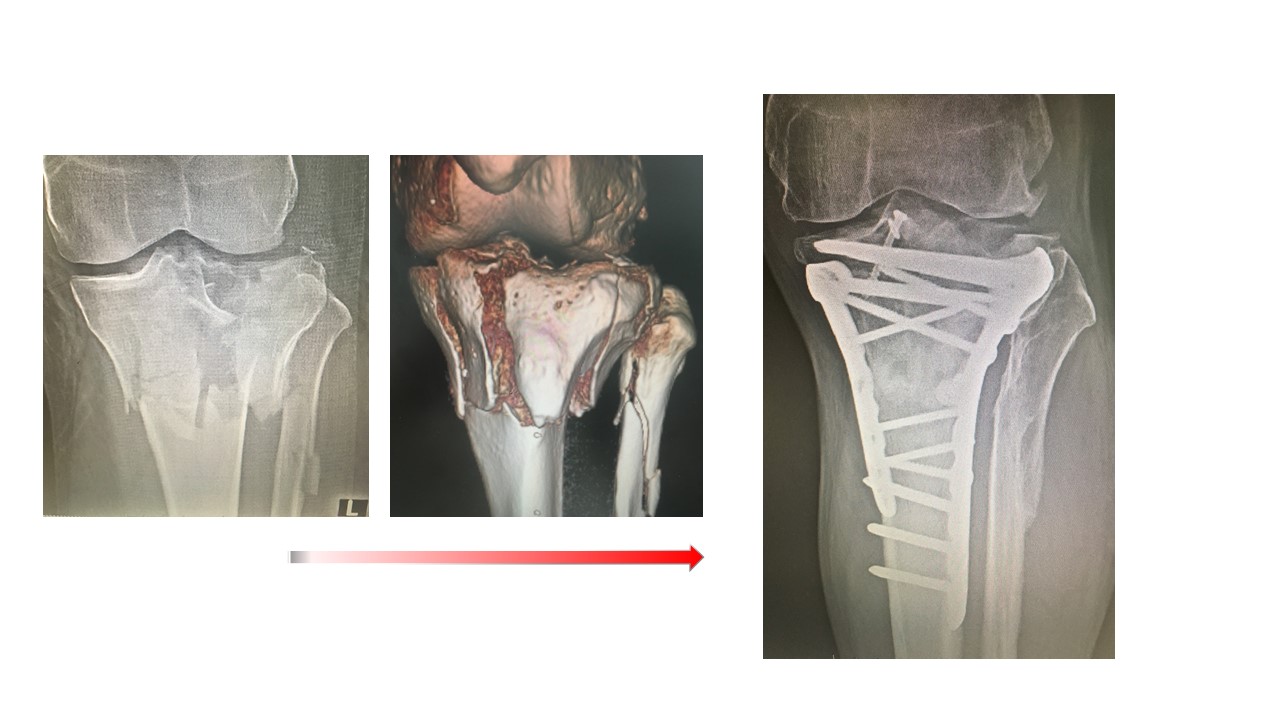

どうしても手術が必要なケガ(保存治療では外見上の問題、機能障害が残る骨折や腱断裂などのケガ)に対しては、早期の治療が必要です。また、手術を行う場合には、傷を小さくすることも重要な治療課題の一つとなります。関節鏡を用いたり、皮膚の切開方法を工夫したりすることにより傷の大きさは大きく変わります。これを最小侵襲手術と呼び、当院では積極的にこの治療法を取り入れております。また、骨折を強固に固定することで術後早期にけがした部位を使用すること(手・肘・肩の使用、歩行など)が可能となり、早期社会復帰、スポーツ復帰が可能となります。

さらに当院では救命センターと連携し、三次救急に搬送される多発外傷、重症四肢外傷、脊椎外傷、骨盤外傷にも対応しております。一般外来に受診される外傷とは異なり、緊急対応を求められることが多く、即時での適切な対応が必要となります。蘇生、救肢、機能再建の3要素を軸とし、集中治療から退院までの集学的治療を救命センターと協力し合いながら行っております。